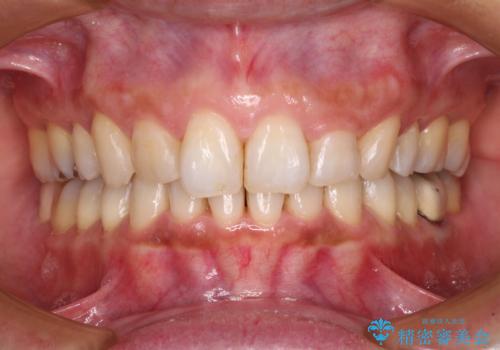

- 以前行った抜歯矯正が後戻りし、開いてしまったスペースが気になるとのことで来院された患者様です。

インビザラインを用いて開いてしまったスペースと前歯のデコボコを改善することとしました。

矯正治療後には気になっていた銀歯をセラミッククラウンやセラミックインレーにて治療することとしました。

上顎前歯を左右対称となるように歯列を整えたいとのことでしたが、すり減って形態が大きく異なっていたため、できる範囲での仕上がりとなりました。